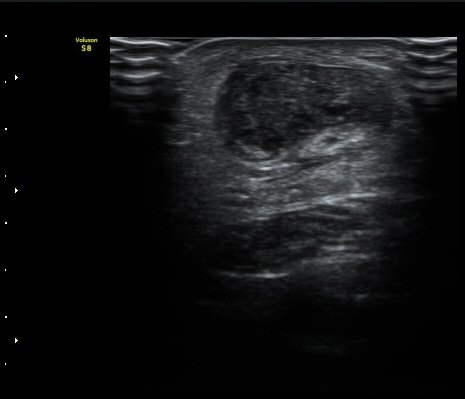

[¹ß¸ñ] ¾ÆÅ³·¹½º ÈûÁÙ ÆÄ¿­ÀÇ ÃÊÀ½ÆÄ Áø´Ü

ÁÂÃø ¹ß¸ñÀÇ ÅëÁõ(2ÁÖ)

2ÁÖ Àü ¹èµå¹ÎÅÏÇÏ´Ù°¡ ¹ß¸ñÀÇ ÅëÁõÀÌ ¹ß»ýÇÏ¿© Ÿº´¿ø¿¡¼­ ÃÊÀ½ÆÄ°Ë»ç µî ½ÃÇàÇÏ°í ºÎ¸ñ°íÁ¤ ÈÄ ¹°¸®Ä¡·á À§ÇØ ³»¿ø

¾ÆÅ³·¹½º°Ç ºÎÁ¾ ¹× ¾ÐÅë, ´Éµ¿Àû ¹ß¸ñ ¹ß¹Ù´ÚÃø ±¼°ñ G 1, thomson test(+).

ÃÊÀ½ÆÄ °Ë»ç